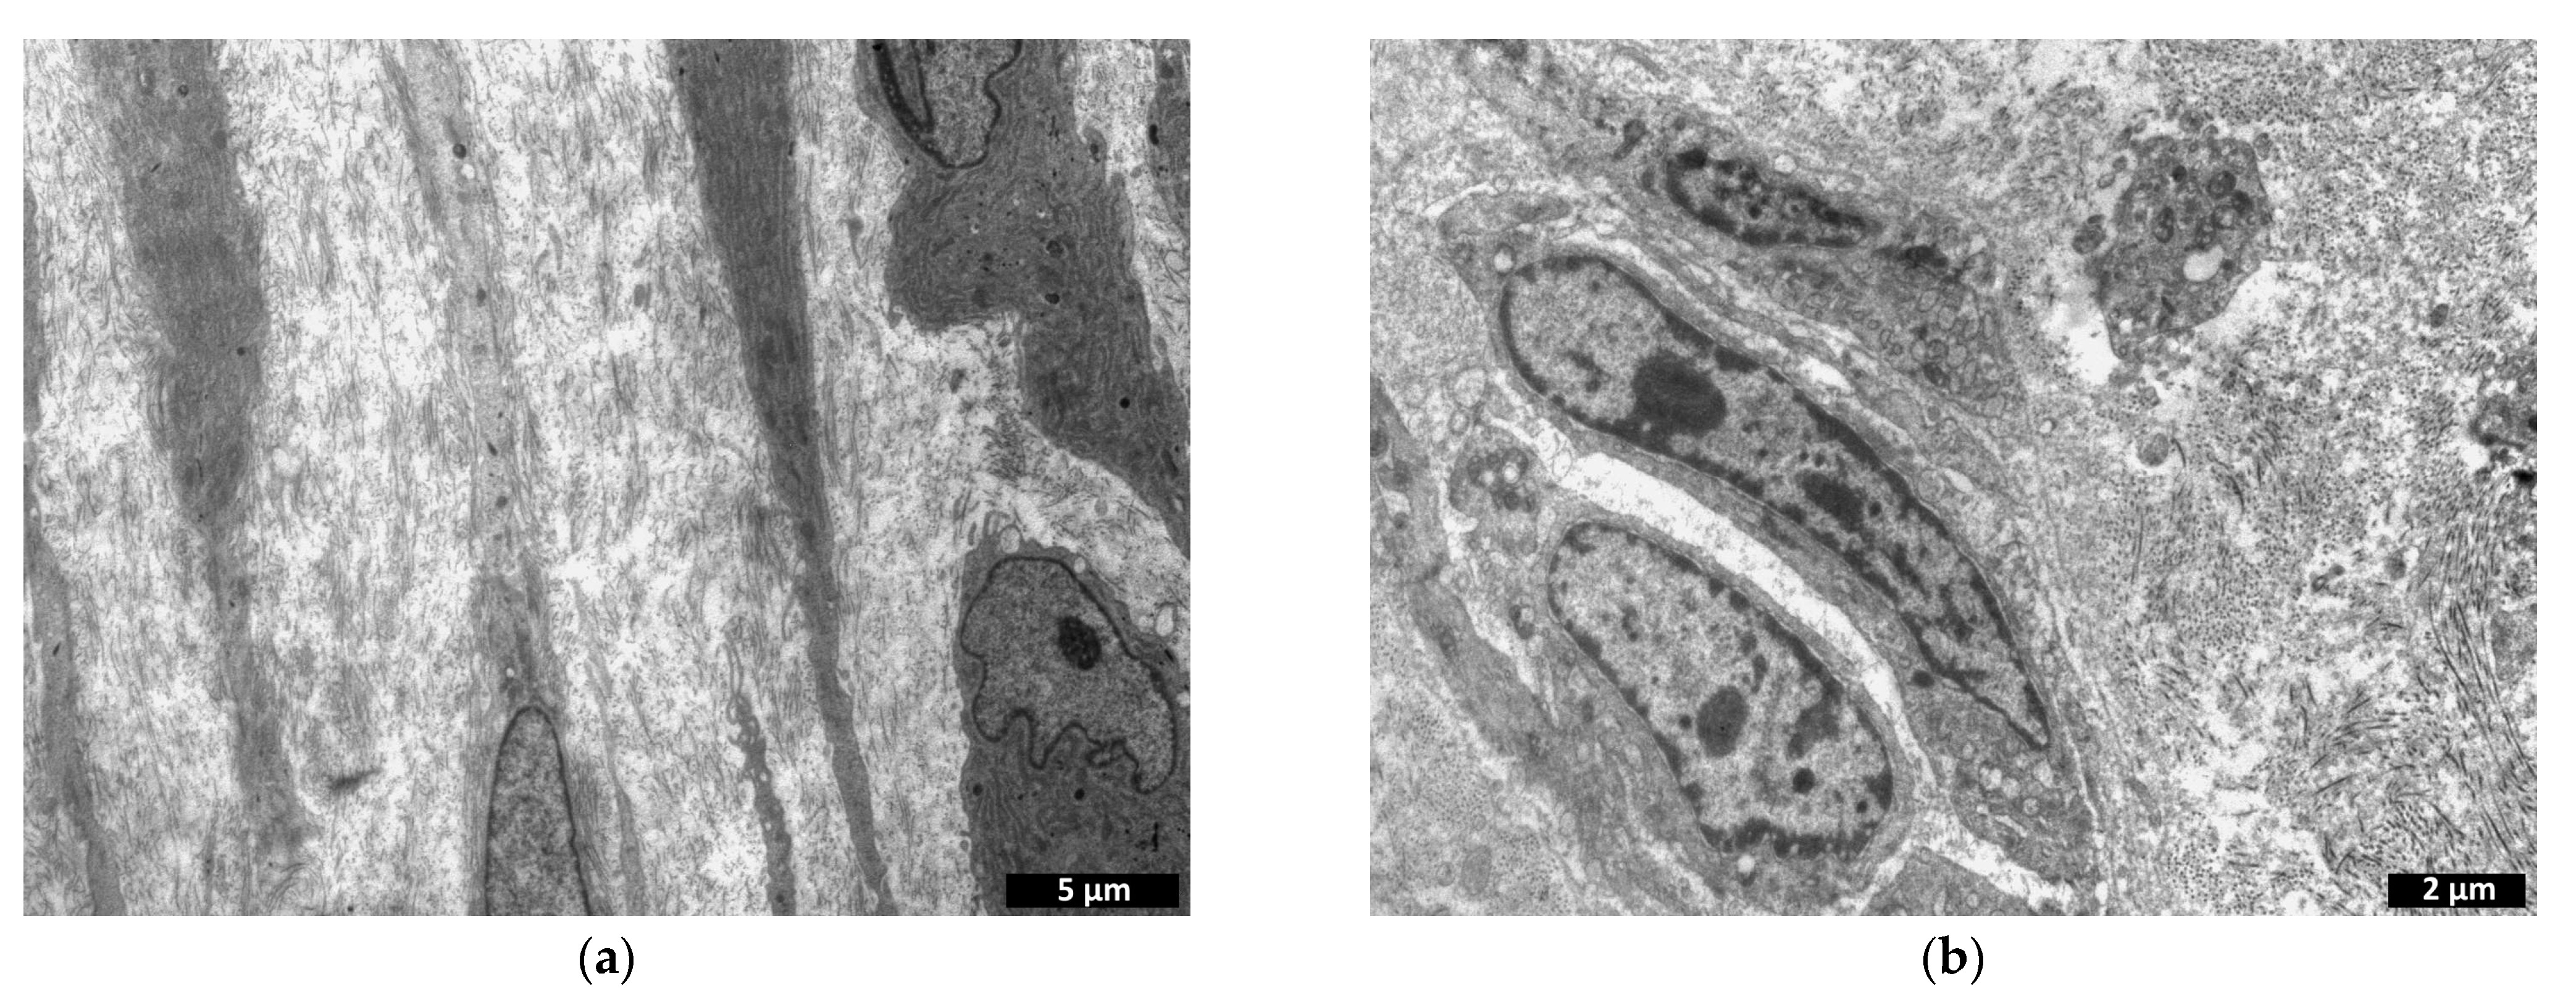

2.5.2. Transmission Electron Microscopy

- Analysis of structural changes in the implant itself without cells: microphotographs obtained at 14,000× magnification (n = 20 from each specimen) were processed using the ImageJ software package (National Institutes of Health). This software package calculates the percentage ratio of the examined area to the entire image area.